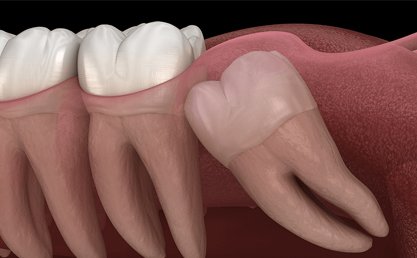

Wisdom Tooth extraction a surgical procedure to remove one or more wisdom teeth , located at the back corners of your mouth on the top and bottom.

• If a wisdom tooth doesn’t have room to grow, results in pain, food entrapment, infection or gum disease, tooth decay infection or other dental problems, you’ll likely need to have it pulled.